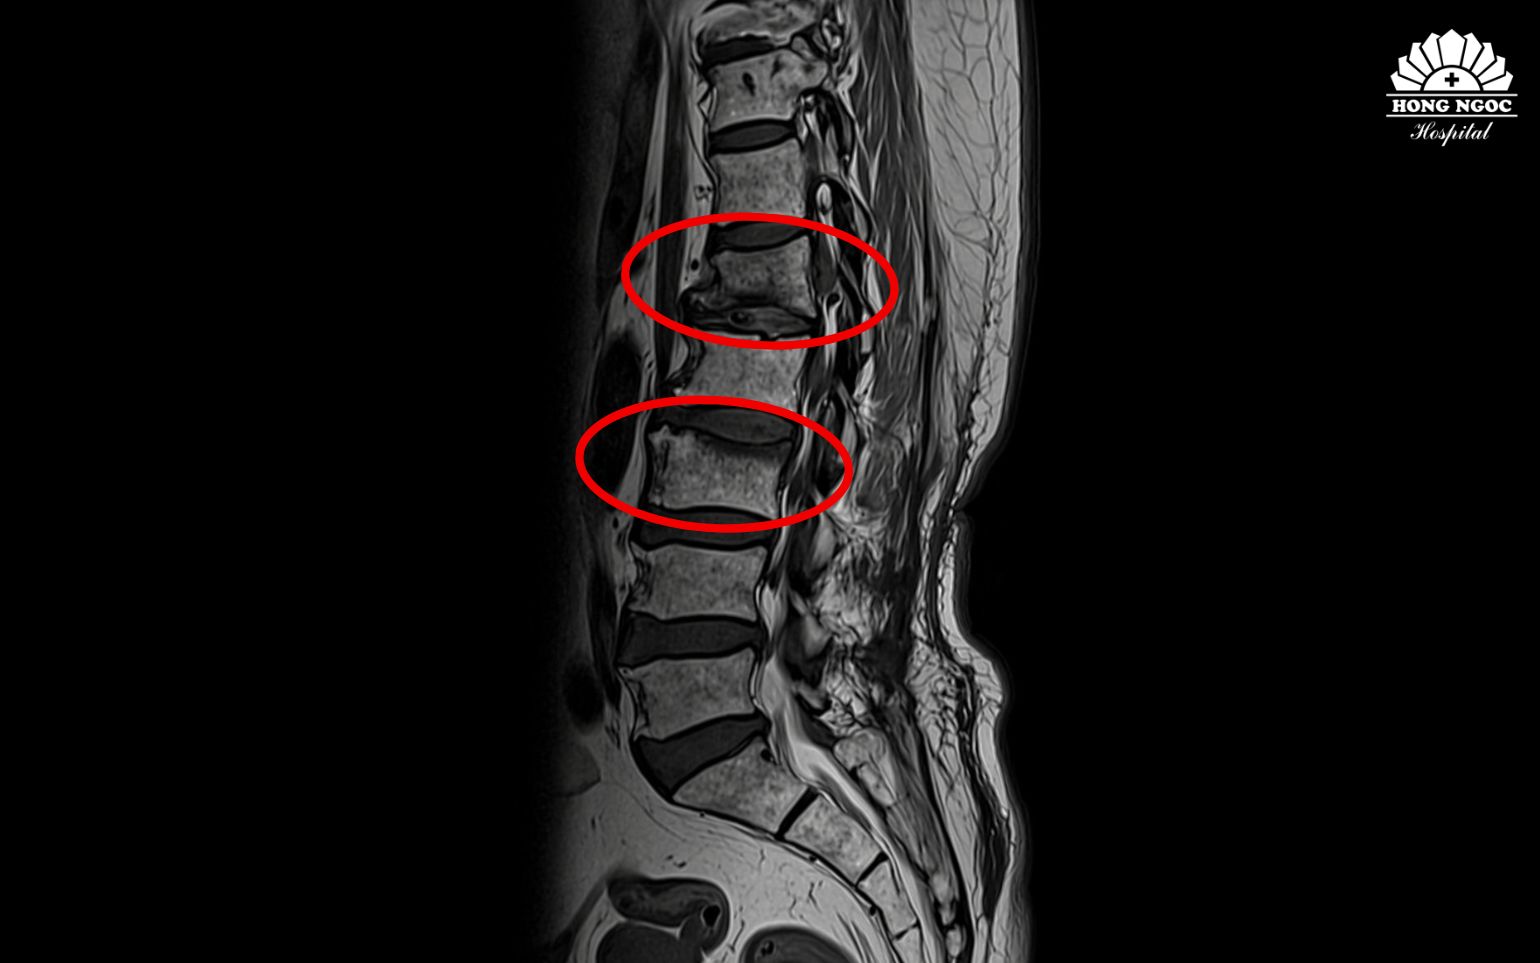

Quyết định đến Bệnh viện Đa khoa Hồng Ngọc (BVĐK Hồng Ngọc) thăm khám, kết quả chụp phim MRI cột sống và xét nghiệm cận lâm sàng ghi nhận bệnh nhân bị: xẹp cùng lúc 2 đốt sống do loãng xương nặng, hội chứng Cushing (do dùng corticoid), tăng huyết áp, rối loạn lipid máu, thiếu vitamin D.

Xẹp đốt sống L1, L3 sau thời gian uống thuốc đông y không rõ nguồn gốc

Corticoid tích lũy trong cơ thể gây ra tình trạng xương giòn và dễ gãy, khiến bệnh nhân bị xẹp cùng lúc 2 đốt sống dù không gặp chấn thương. Đồng thời, tình trạng phù mặt, tăng cân và khó thở ghi nhận ở người bệnh cũng là biểu hiện của rối loạn chuyển hóa và ức chế nội tiết do lạm dụng corticoid. Ngoài ra, việc sử dụng các chế phẩm này còn tiềm ẩn nguy cơ tổn thương gan, thận, tăng huyết áp và suy giảm miễn dịch”.